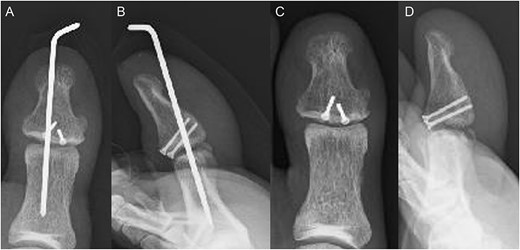

A 54-year-old man injured his right great toe while walking and wearing sandals. He complained of tenderness, swelling, and pain during motion. He could bear weight but could not actively extend the interphalangeal (IP) joint of the hallux. He was referred to our outpatient clinic 3 days after the injury. Physical examination revealed swelling, tenderness, and motion pain, and the patient could not extend the IP joint of the hallux. Plain lateral radiography and computed tomography revealed a displaced avulsion fracture of the dorsal base of the distal phalanx (Fig. 1). Surgery was performed under general anesthesia after informed consent was obtained on posttraumatic day 11. A Y-shaped incision was made at the center of the dorsal IP joint, and the displaced bony fragment was attached to the extensor hallucis longus (EHL). The IP joint was temporarily fixed with a 1.6 mm Kirschner wire, and the fragment was repositioned and fixed with two 1.5 mm cortical screws (APTUS® Hand, Medartis, Basel, Switzerland). A 4-0 FiberWire® (Arthrex, Naples, FL, USA) was fastened as an augmentation proximally to the EHL tendon and distally to the periosteum of the distal phalanx in a figure eight (Fig. 2). Postoperatively, the ankle was externally fixed in dorsiflexion from the leg to the toe, and heel loading was permitted. A total of 4 weeks after surgery, the Kirschner wire was removed to allow active motion of the IP joint of the hallux, and weight bearing was allowed on the hallux 5 weeks postoperatively. Plain radiographs taken 3 months after surgery confirmed bone healing (Fig. 3). A total of 20 months postoperatively, the patient acquired normal function, and the range of motion of the affected IP joint ranged from −3° to 30°, with no difference from the unaffected side (Fig. 4). Skin necrosis or nail deformities were not observed.

Operative findings (A) showed a bone fragment attached to the EHL (arrowhead) and (B) fixed with two screws (arrows). (C) Suture augmentation technique with FiberWire® (dotted line) proximally sutured to the EHL and distally sutured to the periosteum.